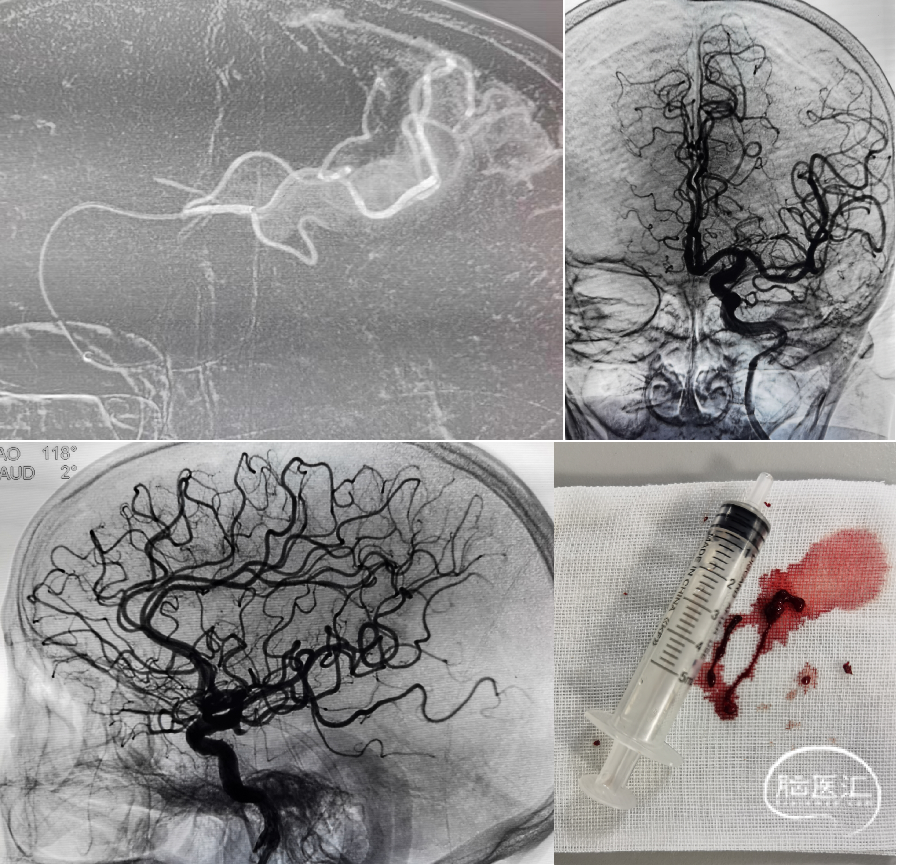

造影证实:双侧大脑前动脉均由左侧发出、双侧大脑前动脉栓塞、左侧大脑中动脉下干远端栓塞。

微导丝+微导管velocity辅助血栓抽吸导管4MAX到达右侧大脑前动脉A2段抽吸,抽吸1次后造影右侧大脑前动脉血流恢复,但左侧大脑前动脉仍闭塞。

微导丝+微导管velocity辅助血栓抽吸导管4MAX超选到达左侧大脑前动脉A3段抽吸,抽吸1次后造影左侧大脑前动脉部分再通、A3段远端仍有栓塞。

微导丝辅助微导管velocity到达左侧大脑前动脉A3段以远抽吸,利用微导管velocity持续抽吸后造影左侧大脑前动脉完全再通、前向血流Ⅲ级;最终双侧大脑前动脉血流恢复、前向血流Ⅲ级;左侧大脑中动脉下干远端栓塞部位血管细小迂曲故未干预、手术结束。

Neuron Max长鞘能高到位,术中提供稳定的支撑;4MAX抽吸导管内径0.041",通过性强,轻松到达A2-A3段进行有效抽吸;Velocity辅助抽吸A3以远段,也带来良好效果。